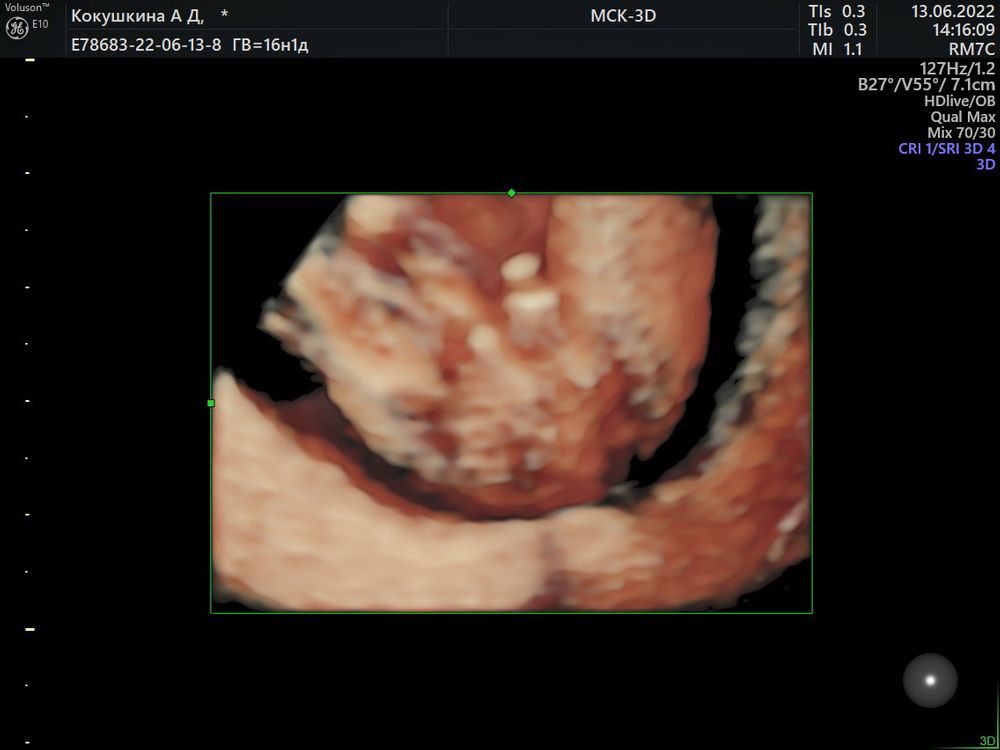

Татьяна  Здесь недель 18 вроде, точно не помню. Вид сверху. На остальных узи только подтверждали. На последнем скрининге показали на экране половые губы,было отлично видно,хотя я до последнего сомневалась😁

Здесь недель 18 вроде, точно не помню. Вид сверху. На остальных узи только подтверждали. На последнем скрининге показали на экране половые губы,было отлично видно,хотя я до последнего сомневалась😁

Здесь недель 18 вроде, точно не помню. Вид сверху. На остальных узи только подтверждали. На последнем скрининге показали на экране половые губы,было отлично видно,хотя я до последнего сомневалась😁

Здесь недель 18 вроде, точно не помню. Вид сверху. На остальных узи только подтверждали. На последнем скрининге показали на экране половые губы,было отлично видно,хотя я до последнего сомневалась😁

Оля Горбачёва, интересно ,а как по первому фото можно пол разглядеть? Я даже бугорка не вижу )) на 3д хорошо видно что мальчик 👍